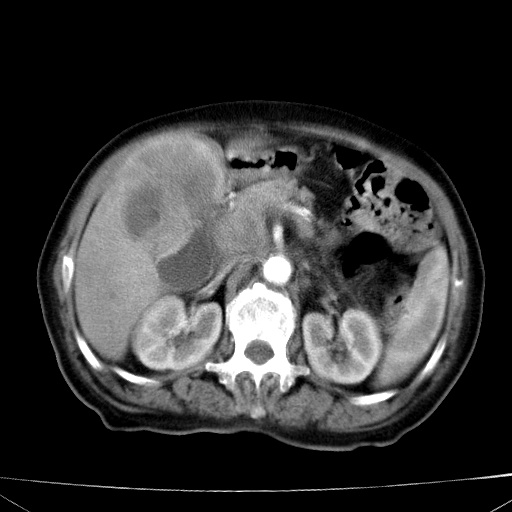

网站人气太旺!昨天的帖子就沉到海底,只好再发贴!ct18338:女 78岁,肝胆病变,已增强,再会诊!原帖链接:http://www.radida.com/bbs/forum.php?mod=viewthread&tid=50032

1)考虑胆囊癌侵犯肝脏并肝门区、腹膜后及右侧膈角后淋巴结转移。2)肝左叶近肝顶部囊肿。3)肝左叶肝内胆管结石。4)左肾近下极囊肿。